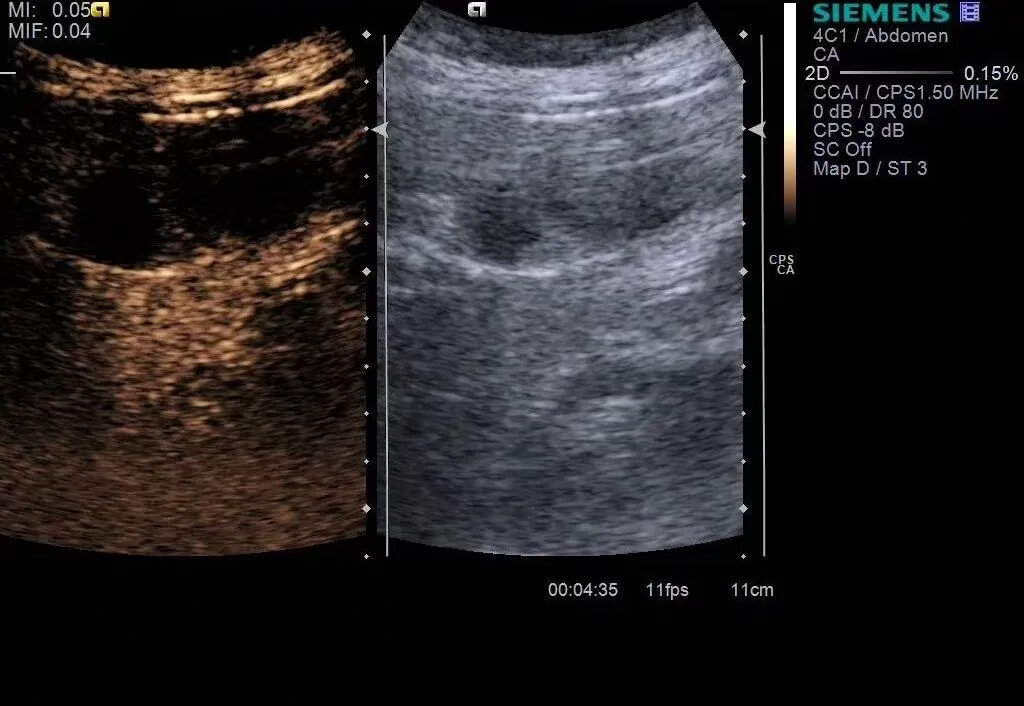

图4 超声造影灌注特征:胆囊底部低回声团块动脉期高于周围肝实质的均匀性高增强,20S达峰

图5 超声造影灌注特征:胆囊内病灶49s造影剂消退,门脉期呈不均匀低增强